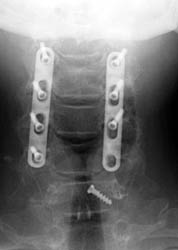

50-year-old male who presented with worsening gait, neck pain, upper

extremity pain, numbness, and occasional bowel and bladder incontinence. The

patient complained of increasing difficulty walking, neck stiffness, and leg

cramps, increasing upper extremity numbness, and dysthesia in hands and

forearms. The patient underwent C3-6 laminectomies with postero-lateral fusions.

AP and lateral radiographs taken 5 days after surgery demonstrate

typical laminectomy defects at C3-6. The posterolateral fusions appear intact

with bone grafting material faintly appreciated. The screws and plates are

intact and in appropriate positioning. |